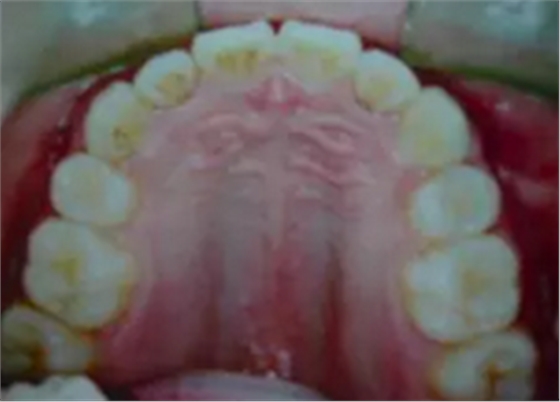

答二、拔牙以后的牙縫在矯治器的作用下,是完全可以關(guān)閉的。

一般來說,拔牙以后的牙縫可以被兩個(gè)方面的牙齒移動(dòng)所關(guān)閉,一個(gè)是前面不齊、前突的牙齒向拔牙間隙移動(dòng),占據(jù)部分拔牙間隙,還有就是后面的大牙也可以向關(guān)(拔牙間隙)移動(dòng),這樣就可以關(guān)閉了這個(gè)間隙。